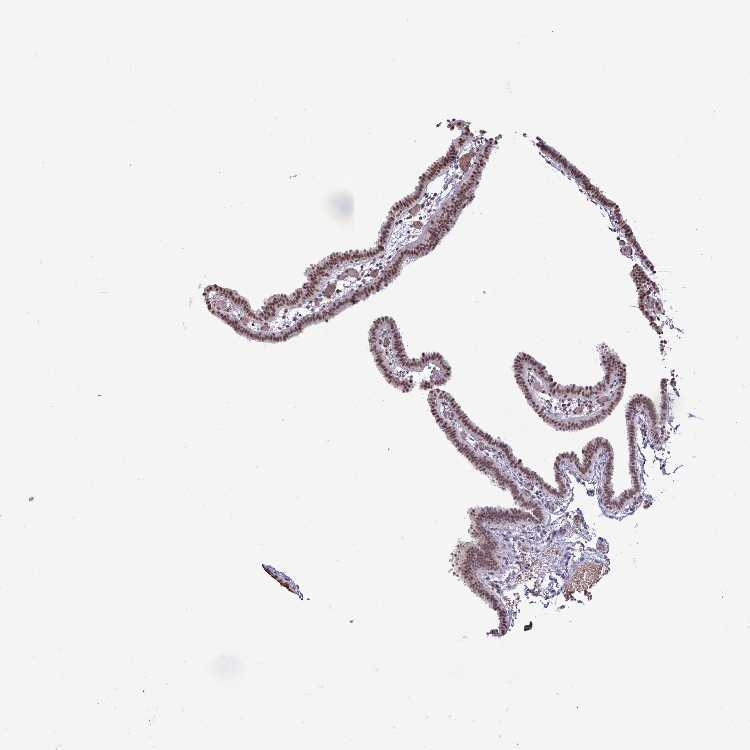

FALLOPIAN TUBE - Antibody stainingi

Antibody staining in the annotated cell types in the current human tissue is reported as not detected, low, medium, or high, based on conventional immunohistochemistry profiling in selected tissues. This score is based on the combination of the staining intensity and fraction of stained cells.

Each image is clickable and will lead to virtual microscopy that enables deeper exploration of all samples and also displays staining intensity scores, fraction scores and subcellular localization as well as patient and tissue information for each sample.

Antibody HPA052096Antibody HPA059714

Ciliated cells (cell body) Medium-

Ciliated cells (cilia axoneme) Not detected-

Ciliated cells (ciliary rootlets) Not detected-

Ciliated cells (tip of cilia) Not detected-

Glandular cells -Medium

Non-ciliated cells Medium-